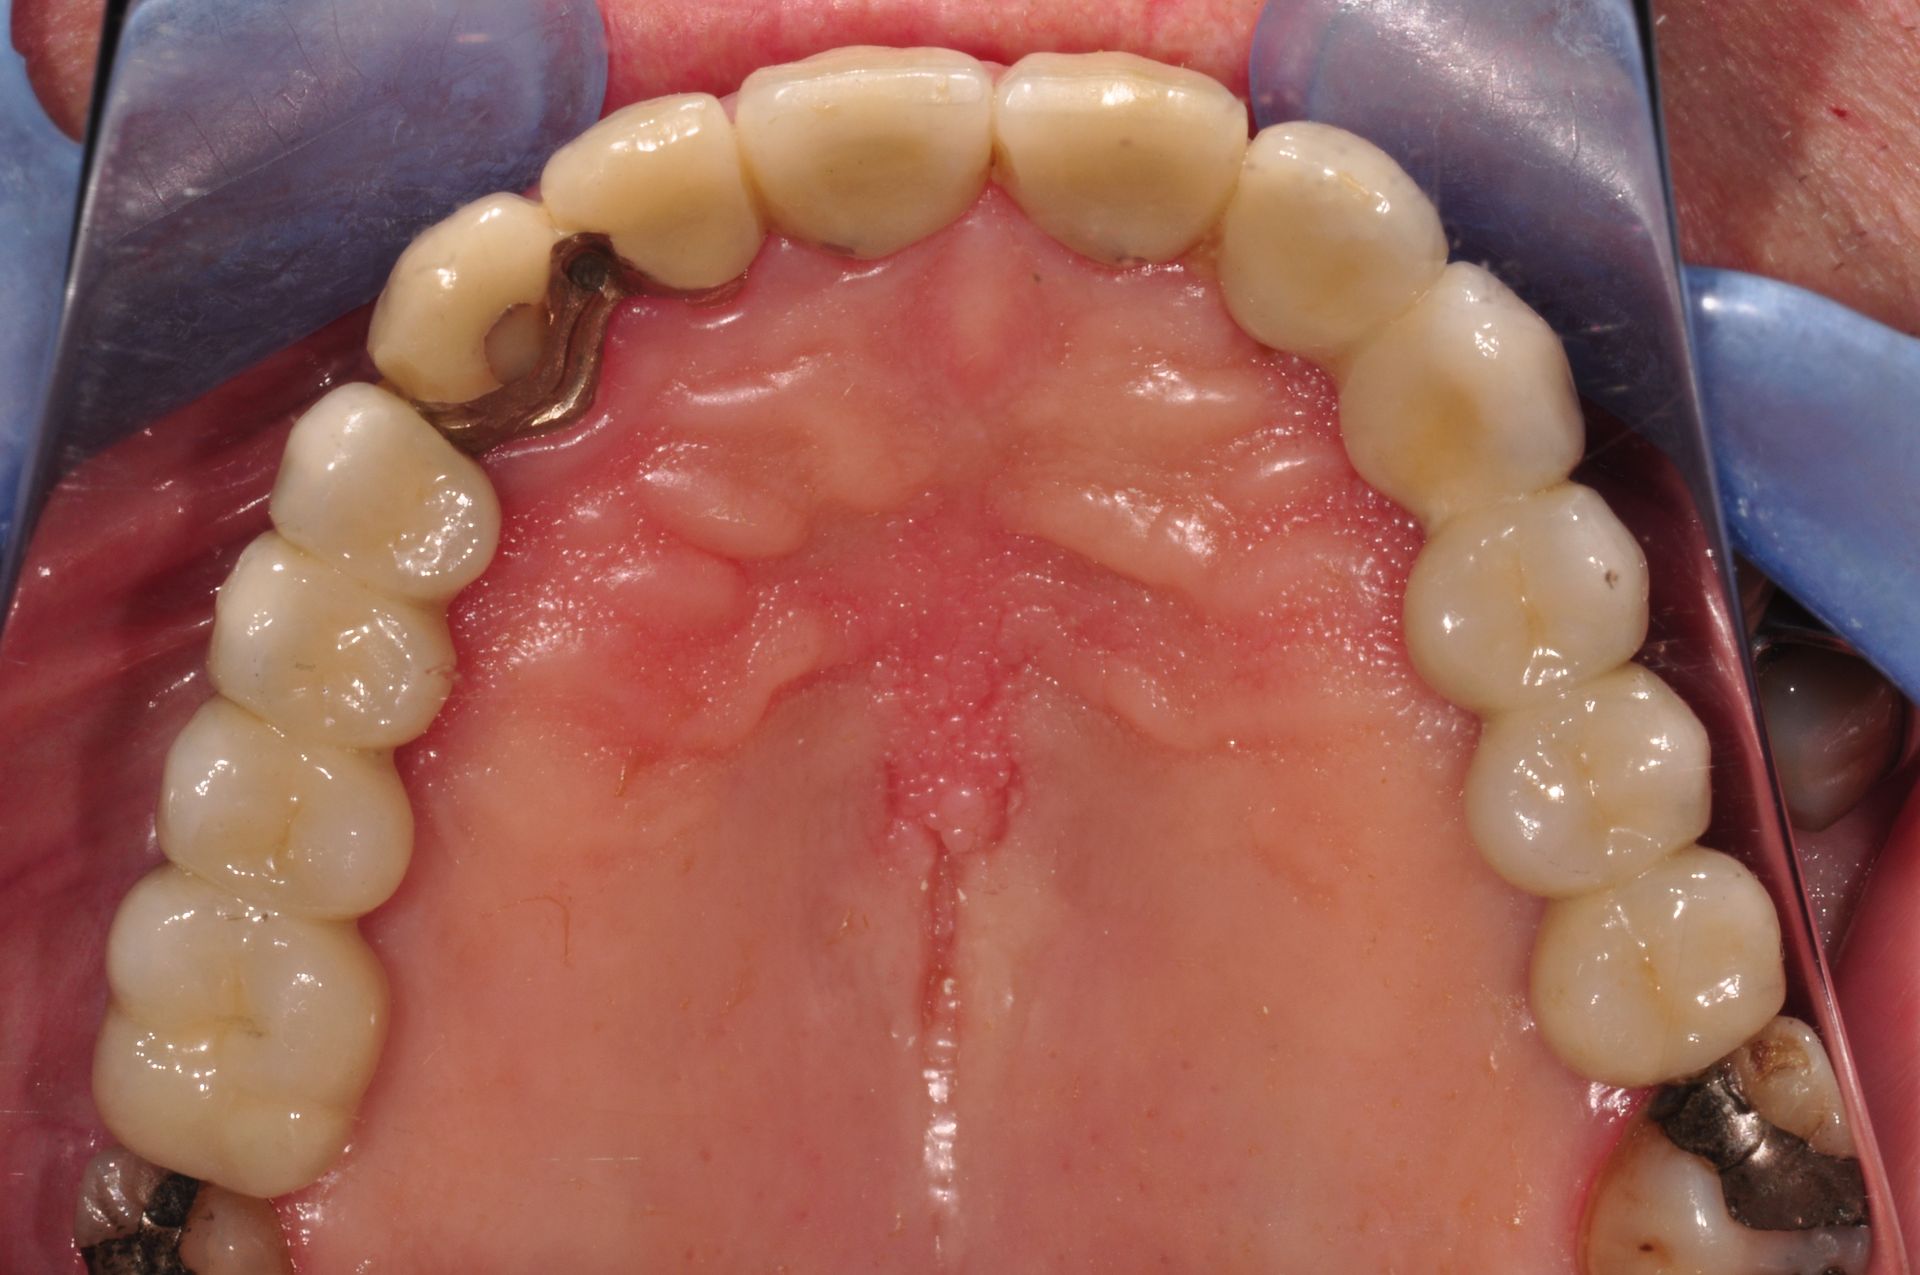

Herausnehmbare Modellguß-Prothese

Vorher: Herausnehmbare Modellguß-Prothese

Feste Zähne mit 8 Implantaten; aus Kostengründen wurden zwei alte Kronen mit dem Goldrand belassen

Nachher: Feste Zähne mit 8 Implantaten; aus Kostengründen wurden zwei alte Kronen mit dem Goldrand belassen